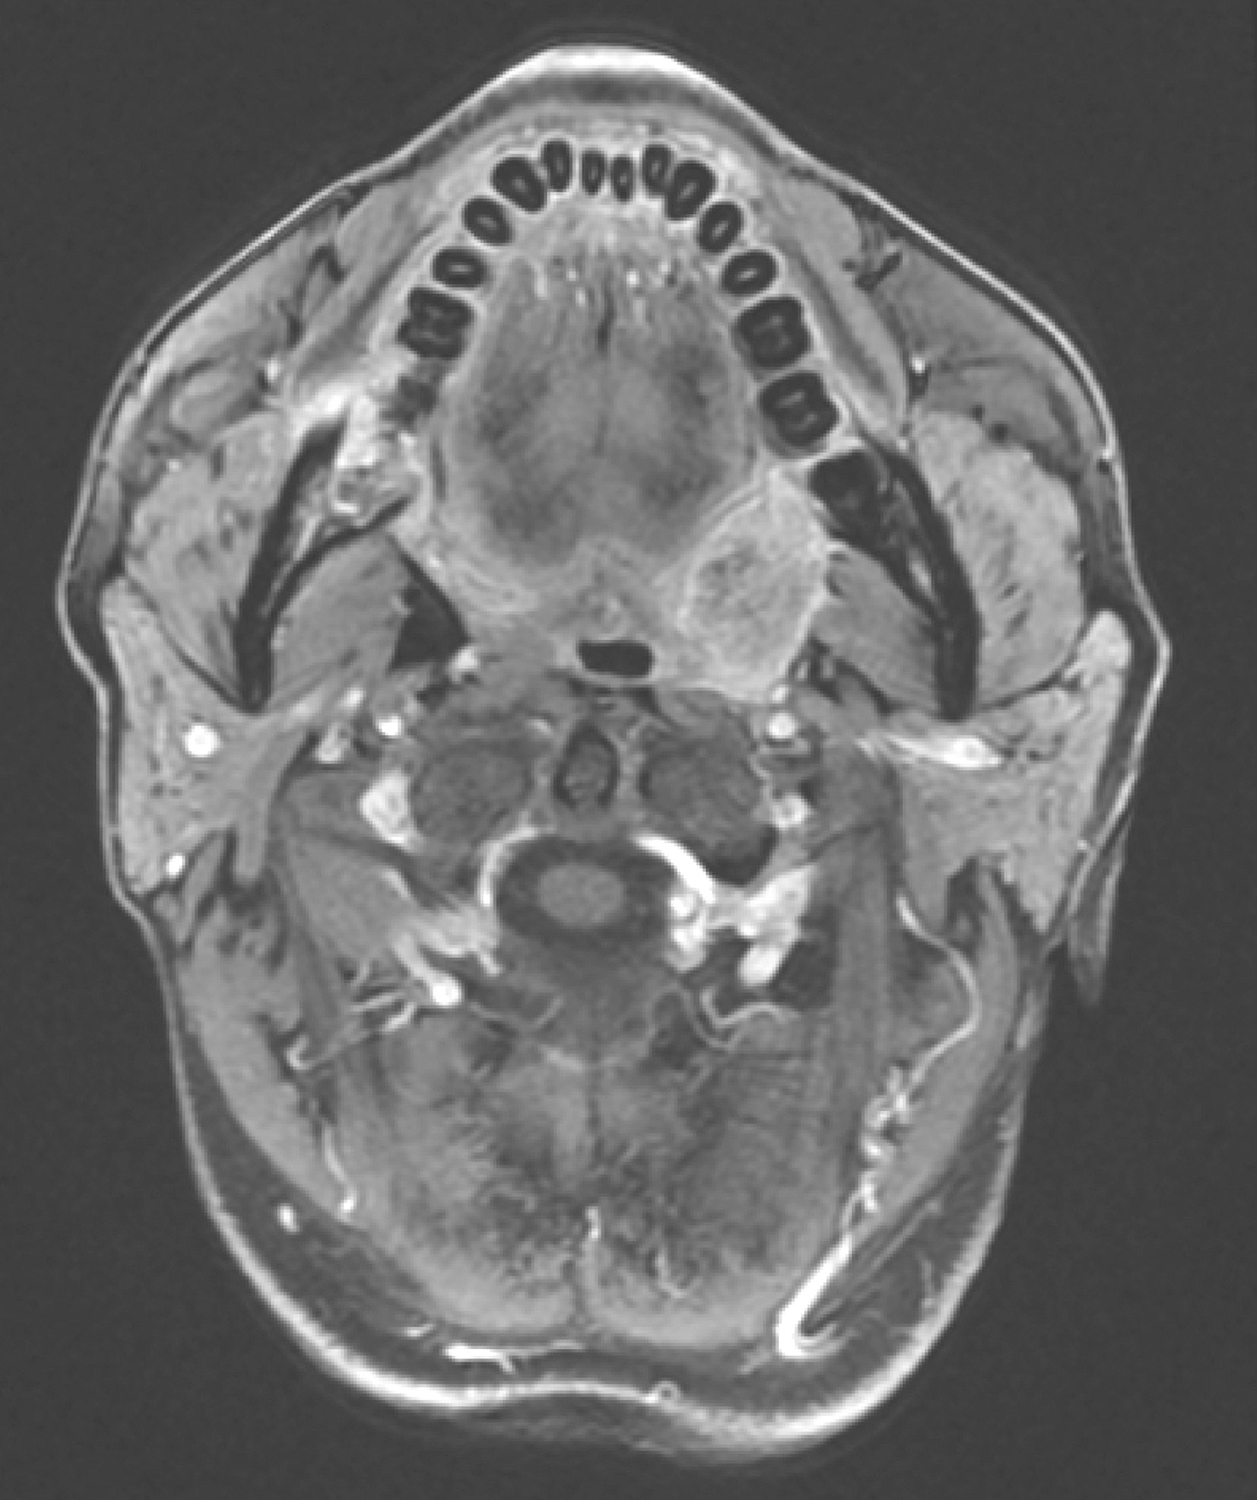

5.2016年10月19日口腔MRI

口咽左侧壁肿物,约2.3cm×1.8cm×2.3cm,T1WI呈等信号,T2WI/FS呈稍高信号,DWI扩散受限,增强扫描明显不均匀强化,肿物向外侵犯左侧咽旁间隙及左侧翼内肌,向下与左侧扁桃体关系密切(图4)。双侧颌下、颈深多发淋巴结,大者短径约0.8cm。

影像学诊断:

(1)口咽左侧壁肿物,考虑恶性,向外侵犯左侧咽旁间隙,贴邻左侧翼内肌,向下与左侧扁桃体关系密切。

(2)双侧颌下、颈深多发淋巴结,请随诊。

图4口腔MRI示口咽左侧壁肿物